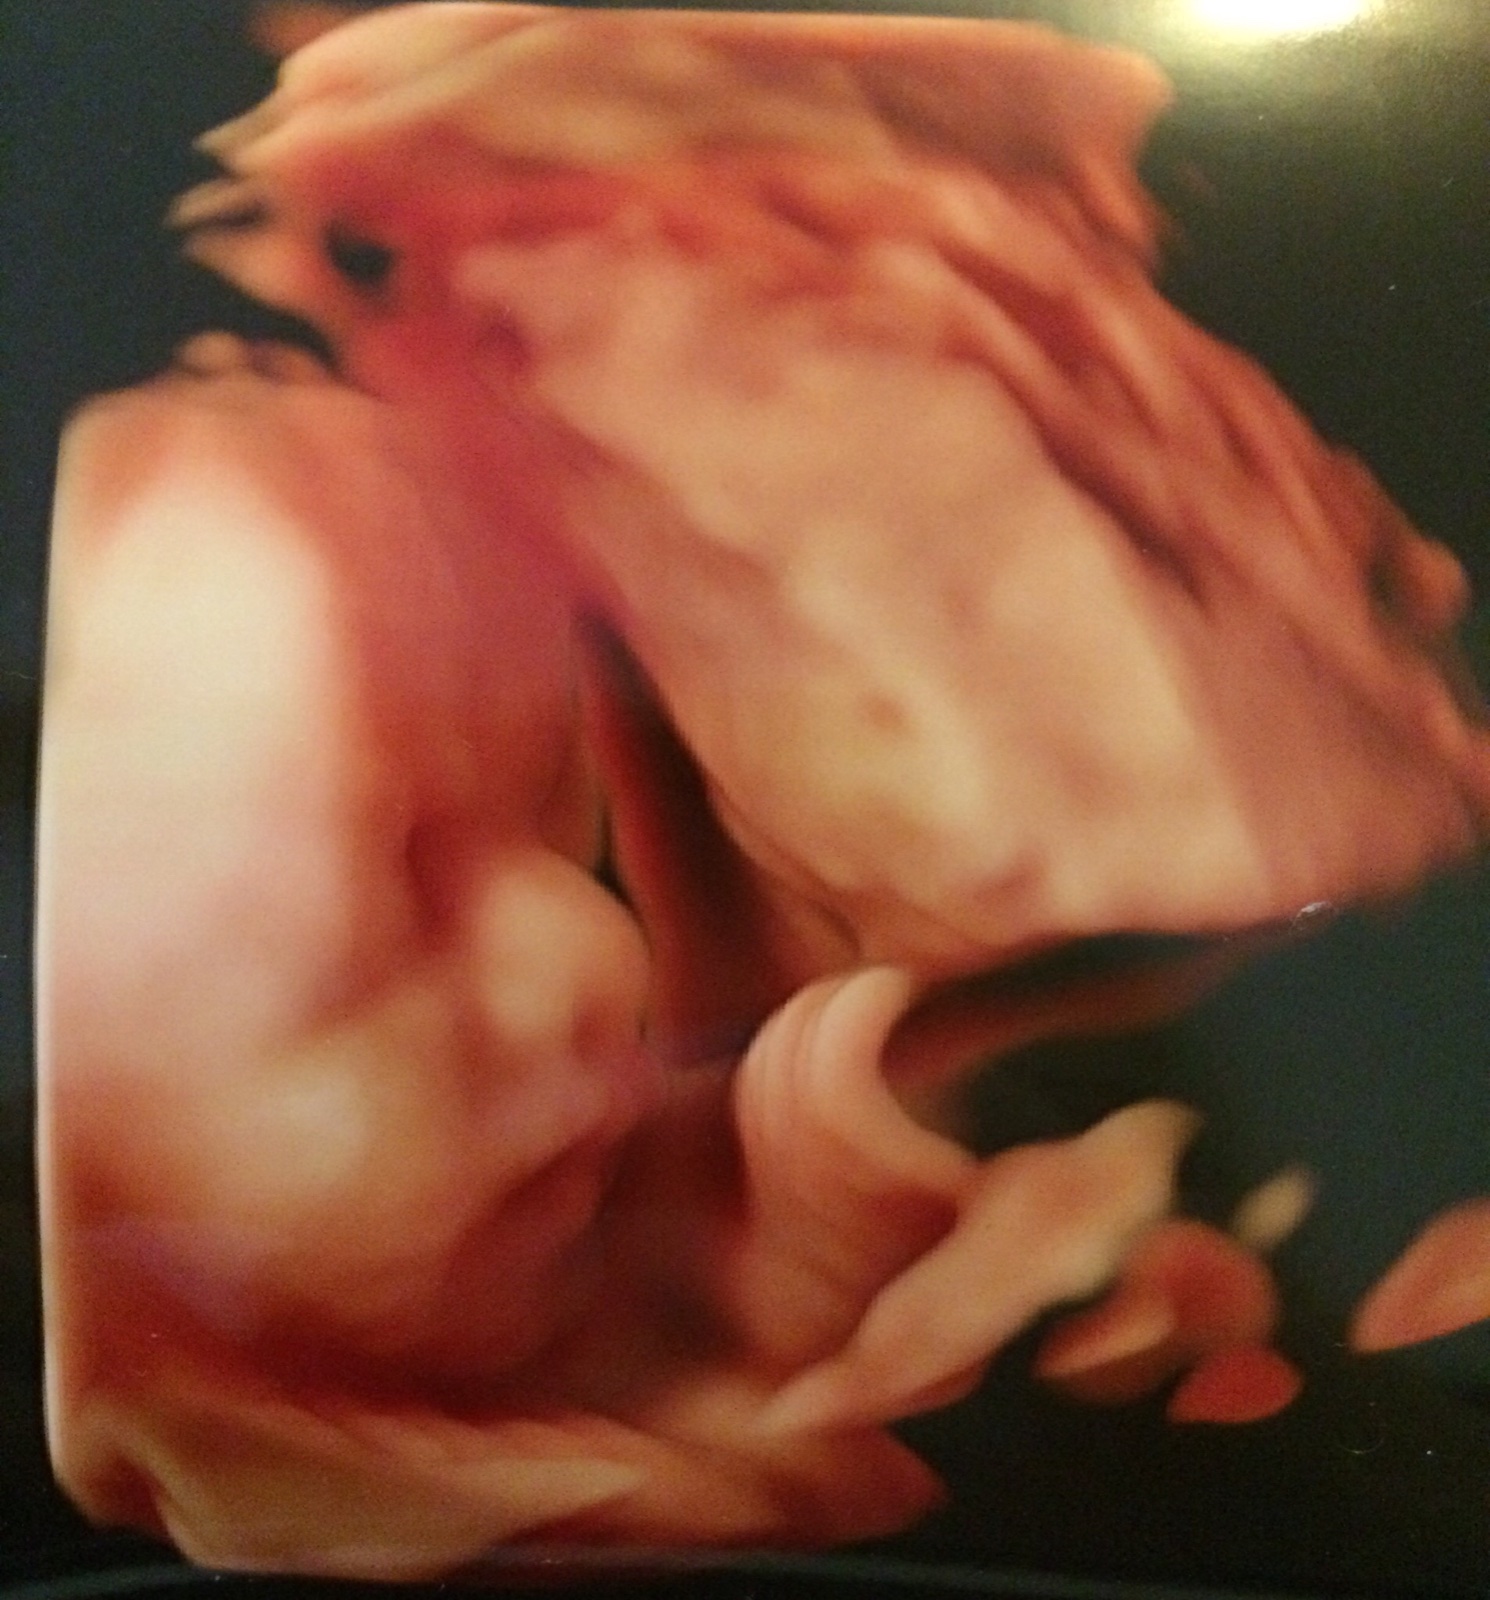

@petula.bir je nádherný miláček ♥ já jdu v úterý na screening a tam se budeme domlouvat na 3D 😀 už se taky moc těším ♥ dnes 19+6 ♥

@petula.bir super 🙂 krásná fotečka,už se moc těšis co 🙂